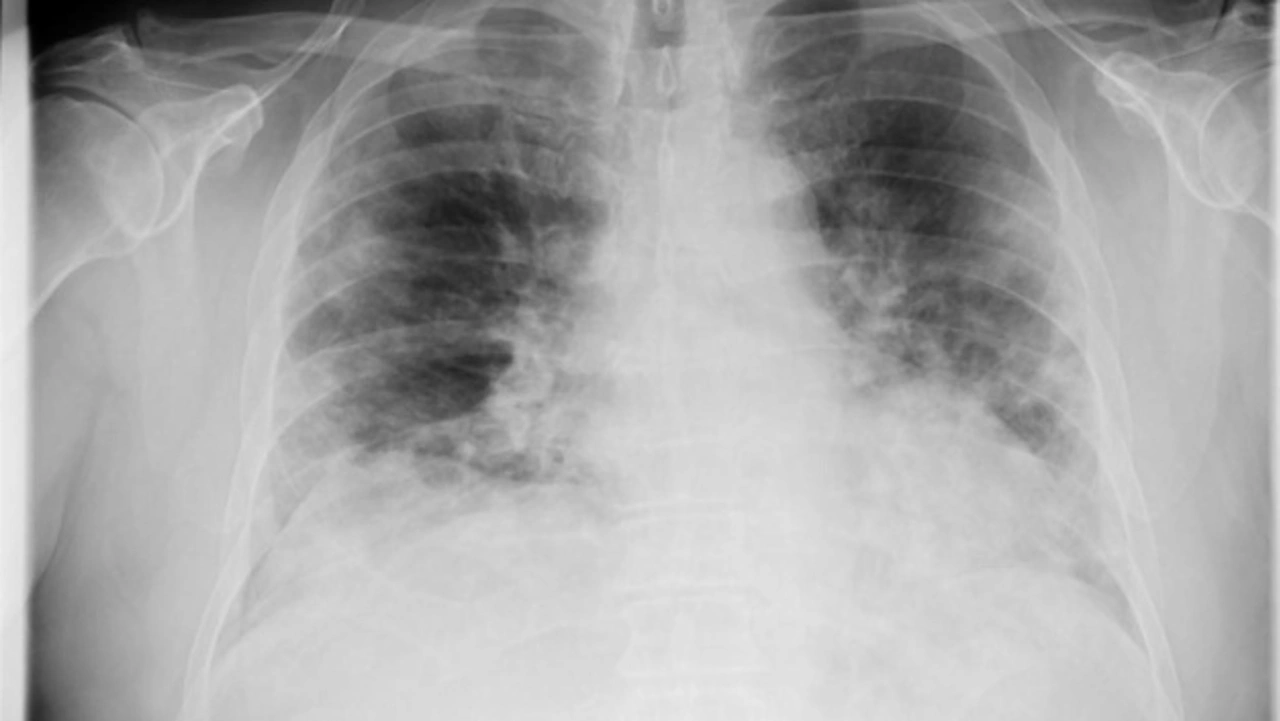

Eine einseitige Veränderung in der Lunge ist ein Hinweis für Bakterien.

So wird zwischen Bakterien und COVID-19 unterschieden